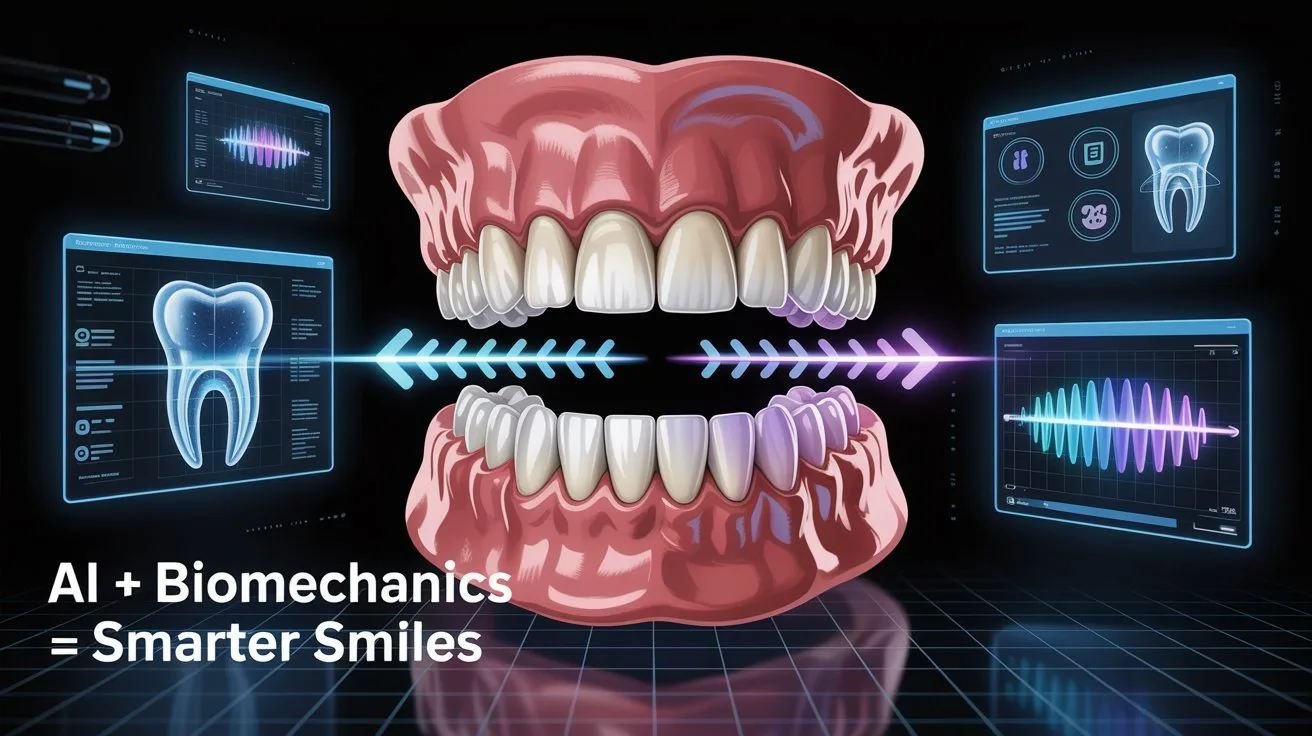

Digital Technology as a Clinical Ally: Integrating CBCT data for routine assessment of bone density and proximity to critical structures, directly aiding in the optimal selection of anchorage sites. Practice sessions utilizing industry-standard software for Virtual Treatment Planning (VTO) optimization based on patient-specific data.

AI in the Refinement Phase: Practical application of Artificial Intelligence for detecting subtle errors in the final alignment (Mid-Course Correction) that may escape the naked eye. Focus on using Scan Registration Analysis software for minute adjustments of aligners or brackets, directly reducing the number of required final refinement appointments.